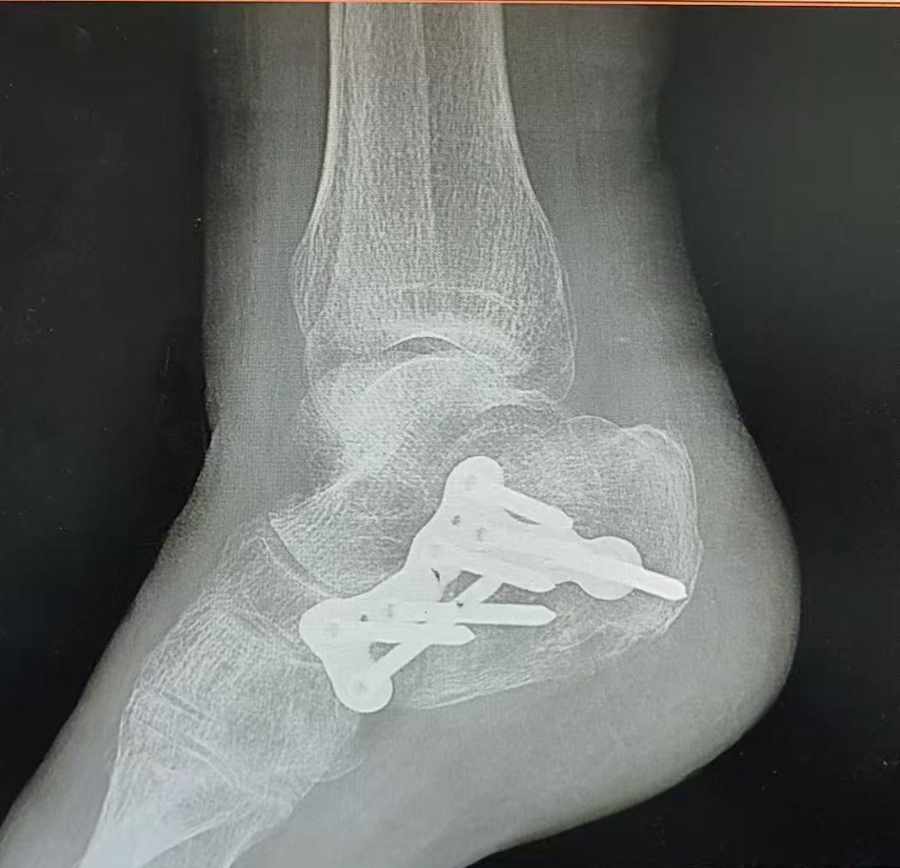

眼见老伴颠仆后失去强劲,孙老伯一时乱了方寸,赶快向前搀扶、连声招呼。一旁的存眷路东谈看法状,主动襄理拨打了120急救电话。大要脱落钟后,救护车抵达现场,将高阿婆送往就近的第十东谈主民病院救治。经CT查抄会诊,高阿婆右侧踝要津、右侧肩要津等共三处骨折,伤情较为严重,需立即剿袭调治。

CT自大多处骨折